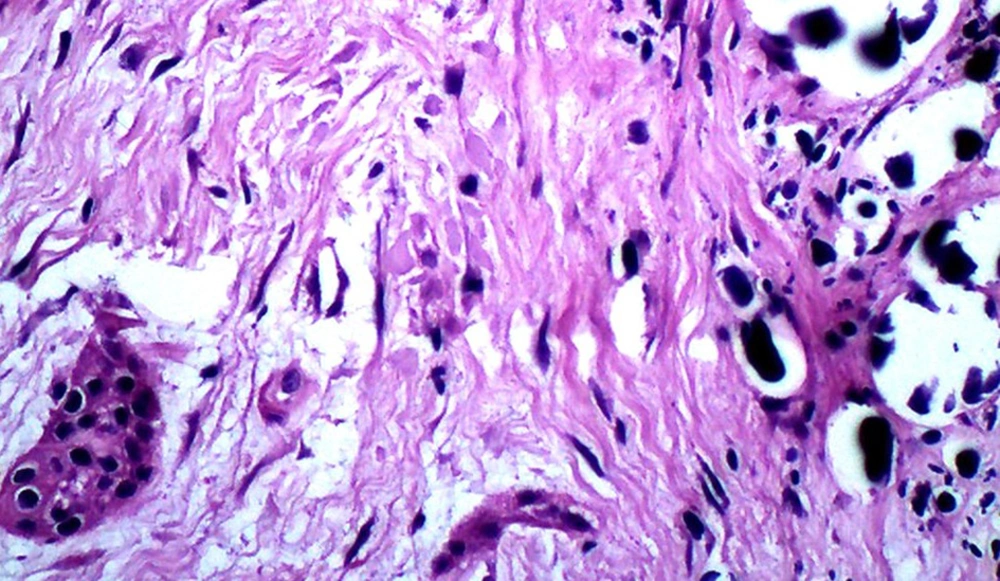

A 13-year-old boy with the chief complaint of multiple unerupted teeth was referred to department of Oral and Maxillofacial Surgery of Ahvaz University of Medical Sciences in May 2013. The panoramic radiograph revealed 15 unerupted teeth (8 in mandible and 7 in maxilla) with large pericoronal radiolucent zone (enlarged follicles) delineated by a well-defined sclerotic borders (Figure 1). Tooth abnormalities such as amelogenesis imperfecta were not seen. Medical and familial history was unremarkable and his siblings had normal dentition. The patient had normal intelligence. He did not have other signs and symptoms like cleidocranial dysplasia, Gardner syndrome, or mucopolysaccharidosis (three syndromes with tendency to multiple impactions). The incisional biopsy was performed with provisional diagnosis of Gorlin syndrome (multiple keratocystic odontogenic tumors). Microscopic examination revealed a dense and cellular fibrous connective tissue with numerous deposits of calcifications. Collagen fibers were arranged in whorled structures. Cords and islands of odontogenic epithelium with numerous clear cells were surrounded by these deposits. Calcifications were found in the whorled areas. There were many small circular droplets of basophilic calcified material resembling cementum. Most of the droplets were homogenous (up to 95%), but some revealed concentric layering similar to Liesegang rings of Pindborg tumor. The diagnosis was atypical follicles with odontogenic fibroma-like changes (WHO type) or hyperplastic calcified dental follicles (Figures 2- 4). Then, the excisional biopsy was performed for mandibular lesions. Grossly, the specimen consisted of multiple pieces of creamy brown soft tissues surrounding the crown of multiple extracted teeth totally measuring 5 × 5 × 1 cm. The lesions showed fine surface nodularities and produced a distinct grating sound during sectioning (Figure 5). The initial diagnosis has been confirmed. Additional surgical procedure must be performed for maxillary lesion in future.